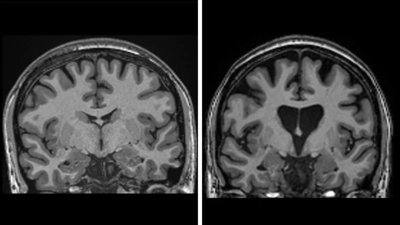

Фото: BBC